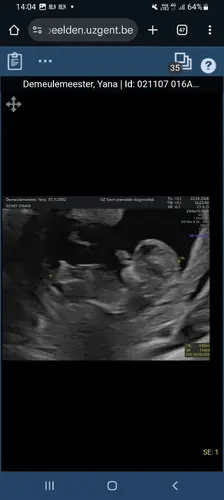

Wij gingen voor de 12 weken (op 13weken) echo maar ik bleek eigenlijk al 14 weken te zijn. De echografist vroeg of we het geslacht al wilden weten en we schrokken dat dit al kon. Zij zei dat aan de hand van de nub theorie ze het kon zeggen met 80% zekerheid. Een jongetje dacht ze, eind volgende week hebben we de uitslag van de nipt en hopen eerst en vooral dat alles oke zal zijn en dan zullen we dus ook met zekerheid het geslacht weten. Ben benieuwd of het juist zal zijn! Ik was er wel van geschrokken dat de echografist zei dat die nub theorie dus wel “redelijk” betrouwbaar is! Ik probeer er allemaal niet teveel mee bezig te zijn, maar ik dacht dat dit een fabeltje was zoals de Ramzi theorie of de Chinese kalender.